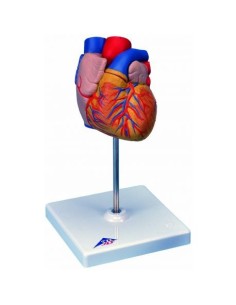

Du crâne en 22 parties à verrouillage magnétique aux modèles de colonne vertébrale, des modèles d'articulation aux modèles de cœur, chaque pièce de notre collection est conçue pour une immersion totale dans l'étude de l'anatomie humaine. Nos modèles, réalisés à partir de scans d'os réels, garantissent une expérience tactile authentique et une fidélité de poids presque identique aux originaux.